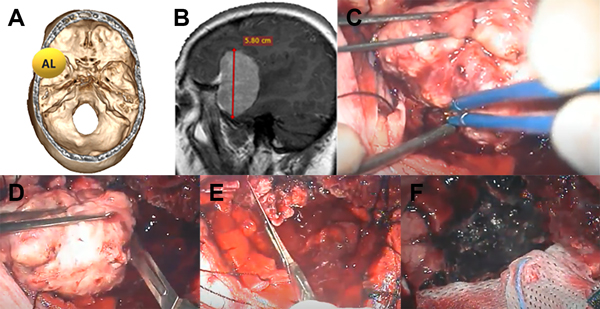

Figura 4: Paciente con meningioma de base de cráneo anterolateral (AL) (1 punto), tamaño más de 5 cm (2 puntos) sin invasión ósea (1 punto), total: 4 puntos, moderada probabilidad de resección total. A: localización de lesión en base de cráneo. B: resonancia con contraste corte sagital prequirúrgica. C: imagen intraoperatoria en donde se observa meningioma con plano aracnoideo. D: vaciamiento y reducción de tamaño con bisturí hoja 11. E: resección parcial de duramadre y coagulación de la misma. F: lodge quirúrgica sin remanente tumoral, resección Simpson 2.